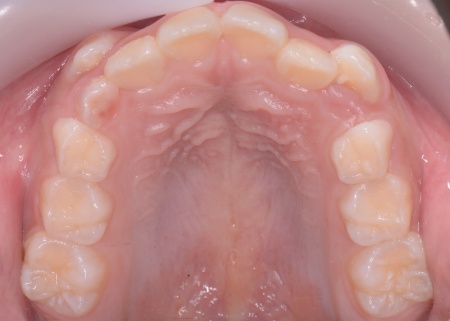

| カウンセリング | 拝見したところ、上の犬歯が歯列の外側に飛び出すように生えている、いわゆる八重歯でした。 さらに、上下の歯全体がデコボコに生えている「叢生(そうせい)」と呼ばれる状態で、これは歯が正しい位置に並ぶためのスペースが不足していることが原因だと考えられます。 このまま放置して顎の成長が完了してから矯正治療を行う場合、歯を並べるスペースを確保することが難しく、永久歯を抜く処置が必要になるケースがあります。 以上のことから、今の段階で歯並びを整える治療が必要だと診断しました。 |

患者様のご家族は「将来的な抜歯はできるだけ避けたいので、今のうちに治療をしたい」と希望されたため、成長期の段階で歯列を広げ、歯が並ぶスペースを確保する小児期の矯正治療「1期矯正」を提案しました。

メリット デメリット また、治療にあたりお口全体のバランスを確認したところ口元の突出はなく、顎のサイズはやや小さめですが、成長期であることから歯列の拡大が可能な状態だと判断しています。 以上の内容について丁寧に説明し、治療に同意いただきました。 まず、上顎に顎の骨を広げるための固定式の矯正器具「急速拡大装置」を、下顎には歯並びの幅を広げるための「リンガルアーチ」を装着します。 次に歯の位置を整えるため、ワイヤー矯正を開始します。 最後に、歯並びが整って見た目や噛み合わせにも問題がないことを確認し、装置を取り外して第1期矯正治療を終了しました。 現在も経過観察を継続していますが、歯が元の位置に戻る後戻りも見られず、残っている乳歯から永久歯への生え変わりも順調に進んでいます。 |